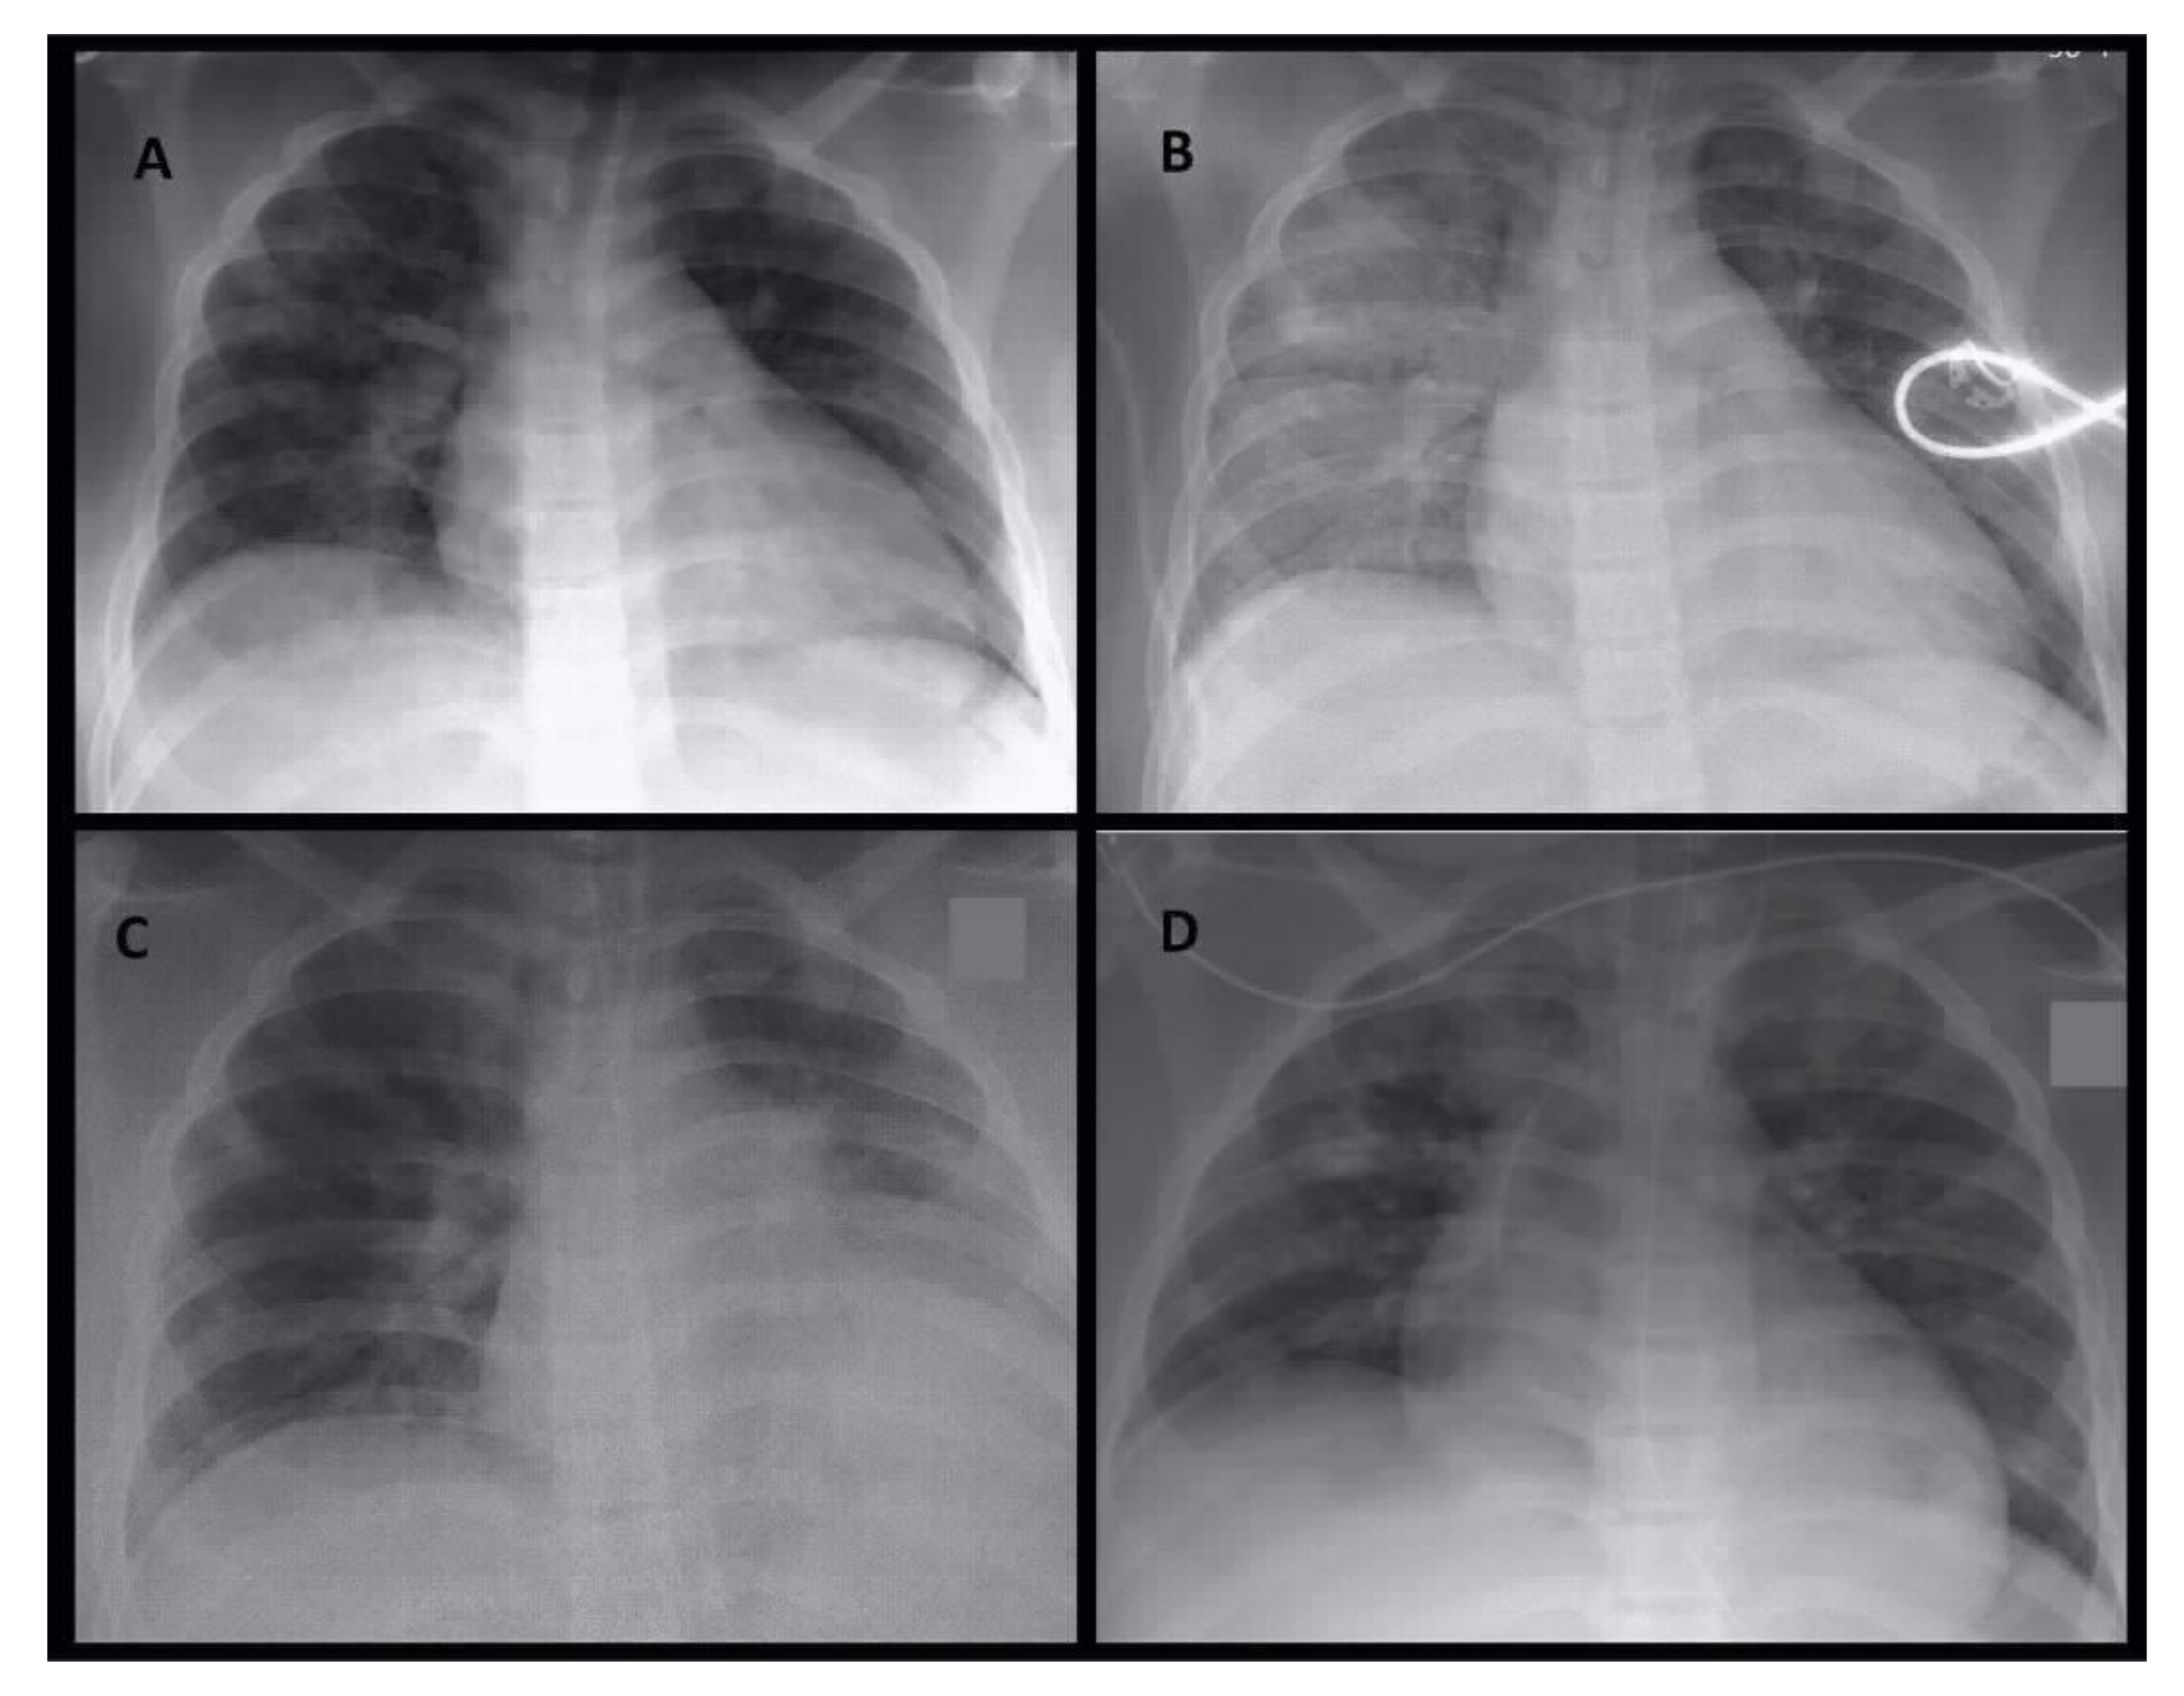

A CT scan showed extensive bilateral patchy areas, subpleural and peribronchovascular consolidations with surrounding ground-glass opacity, extensive consolidations in the lower lobes of both lungs matching to a severe pneumonia and clinically emerging ARDS. Moreover, it showed an extensive sinusitis of the right sinus frontalis, maxillaris and right cellulae ethmoidales. The images of Figure 1 show the radiological evidence in the performed chest X-rays, Figure 2 the sequential CT imaging.

Figure 1.

Serial conventional chest X-ray images on day 1 in the morning (A), on day 1 at noon (B), on day 4 (C) and day 5 (D). On initial X-ray image (A) patchy areas of peribronchovascular infiltrations were detectable. During the same day, ventilation situation became worse with progressive areas of infiltration and retrocardial consolidation (B). These radiological image represent the effect of the infection and not the ventilation. During the stay in intensive care unit ventilation of right side intermediately improved combined with partial atelectasis of left lover lobe (C). On day 5 circumscribed areas of consolidations became obvious (D), leading to subsequent CT imaging.